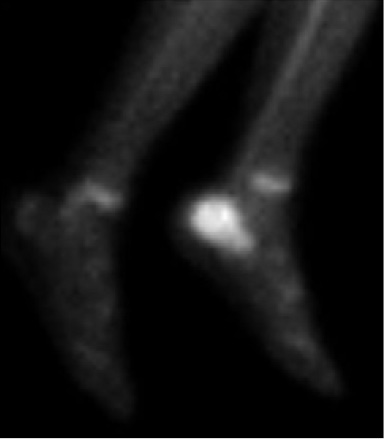

La gammagrafía ósea fue realizada en 3 pacientes, con el 100% de positividad para infección (Figura 4).

Figura 4. Gammagrafía ósea en fase tardía del paciente anterior con osteomielitis de calcaneo izquierdo. Se observa aumento en la captación ósea del radiotrazador en el calcáneo con compromiso infeccioso o inflamatorio. Imágenes propias de los autores.